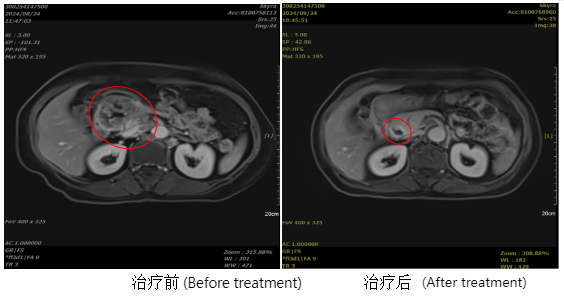

Patient, female, 67 years old, with pancreatic adenocarcinoma of the head, staged as cT3N2M1, stage IV.